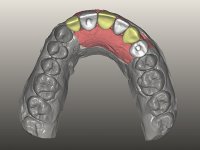

O paciente foi observado conjuntamente e a dúvida que surgiu de imediato foi se seria possível com a regeneração óssea a efectuar poder ser reabilitada naturalmente a zona das papilas interdentárias. Nesse sentido foi feito um enceramento de diagnóstico que contemplaria as duas hipóteses, utilizando ou não a cerâmica gengival. A confecção desse enceramento foi fundamental para expor ao paciente a dificuldade da reabilitação. O wax-up deu origem a um mock-up que foi aprovado pelo paciente e que simultaneamente serviu de guia imagiológica. O caso foi planificado cirurgicamente e realizada uma guia cirúrgica com que foram colocados os implantes. Após 10 semanas foi feita a 1ª impressão para confecção da ponte provisória. Foram criados os primeiros perfis de emergência na gengiva artificial e foi digitalizado o modelo. Por processo de CAD-CAM foi confeccionada uma ponte provisória aparafusada baseada no enceramento de diagnóstico. A ponte trabalhou durante 8 semanas os tecidos moles que foram fielmente copiados numa impressão com técnica de moldeira aberta. Os transferes foram individualizados com resina composta para copiarem fielmente os perfis de emergência criados pela ponte provisória. Confeccionado o modelo de trabalho definitivo, foi realizada uma infra-estrutura em zircónio seguindo a orientação do enceramento de diagnóstico. O assentamento da infra-estrutura foi testado em boca e simultaneamente foi novamente impressionados os tecidos moles com um silicone fluido. Nessa consulta foi feito o levantamento da cor. Os dentes 13 e 23 apresentavam uma saturação anormalmente forte que resolvemos não valorizar, optando por privilegiar a relação com o sector antero-inferior. Foi realizada uma nova gengiva artificial com a impressão que acompanhou a impressão de arrasto com a infra-estrutura. Após a colocação da cerâmica na infra-estrutura foram coladas as meso-estruturas. O trabalho final foi aparafusado lentamente permitindo a adaptação dos tecidos moles.